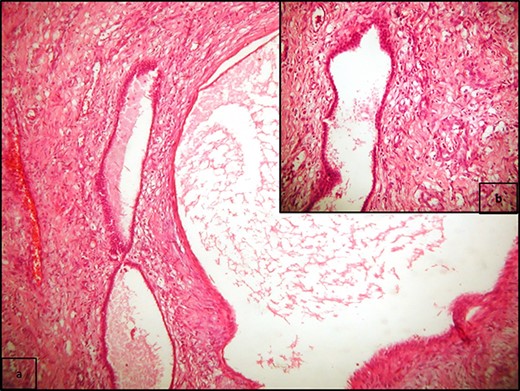

A 20-year-old Caucasian woman presented herself to the outpatient department because of a mass on the left kidney. The mass was an incidental finding in an abdomen computed tomography (CT), which was suggested within the diagnostic evaluation for a persistent flank pain. In the past, she never had any pathologic urologic situation. According to the CT finding, the mass was located on the lower pole of the left kidney (83 × 111 × 111mm) and there was no other pathologic finding. Anamnestically, she had heterozygous beta Mediterranean anaemia. The patient was obese (body mass index = 33.4 kg/m2). We proceeded with a thorax CT which revealed no pathology. The patient underwent a laparoscopic nephrectomy by an urologist well trained and experienced in laparoscopy. Macroscopically, a mass in the lower pole of the left kidney (110 × 100 × 100 mm) was documented. Cut sections revealed multiple thin walled, non-communicating cysts of varying sizes with smooth lining without solid component. Microscopically, the tumor was characterized of cysts separated by thin septa. The cysts lined by single layer of flat, cuboidal and hobnail epithelium and the septa were fibrous, hypocellular to hypercellular. No mitoses or necrosis were identified. The immunohistochemical examination showed that the epithelial cells were positive for the cytokeratins AE1/AE3 and PAX-8. The stromal cells were positive for the progesterone receptors, estrogen receptors and CD10. The latter was concentrated around epithelial elements (Figs 1 and 2). These findings established the diagnosis of ACN. At the 12-month follow-up control with abdomen CT, there was no pathologic finding (Fig. 3). The patient is under urologic and nephrologic montitoring without any abnormal finding at 21 months after surgery. This research complies with the guidelines for human studies and was conducted ethically in accordance with the World Medical Association Declaration of Helsinki.

(a) PR positivity in the stromal spindle cells (PR x400), and (b) strong nuclear PAX8 positivity in epithelial cells (PAX8 x100); (c) high power view of 2a (PR x100); (d) CD10 positivity in the stromal spindle cells, concentrated around epithelial elements (CD10 x100).